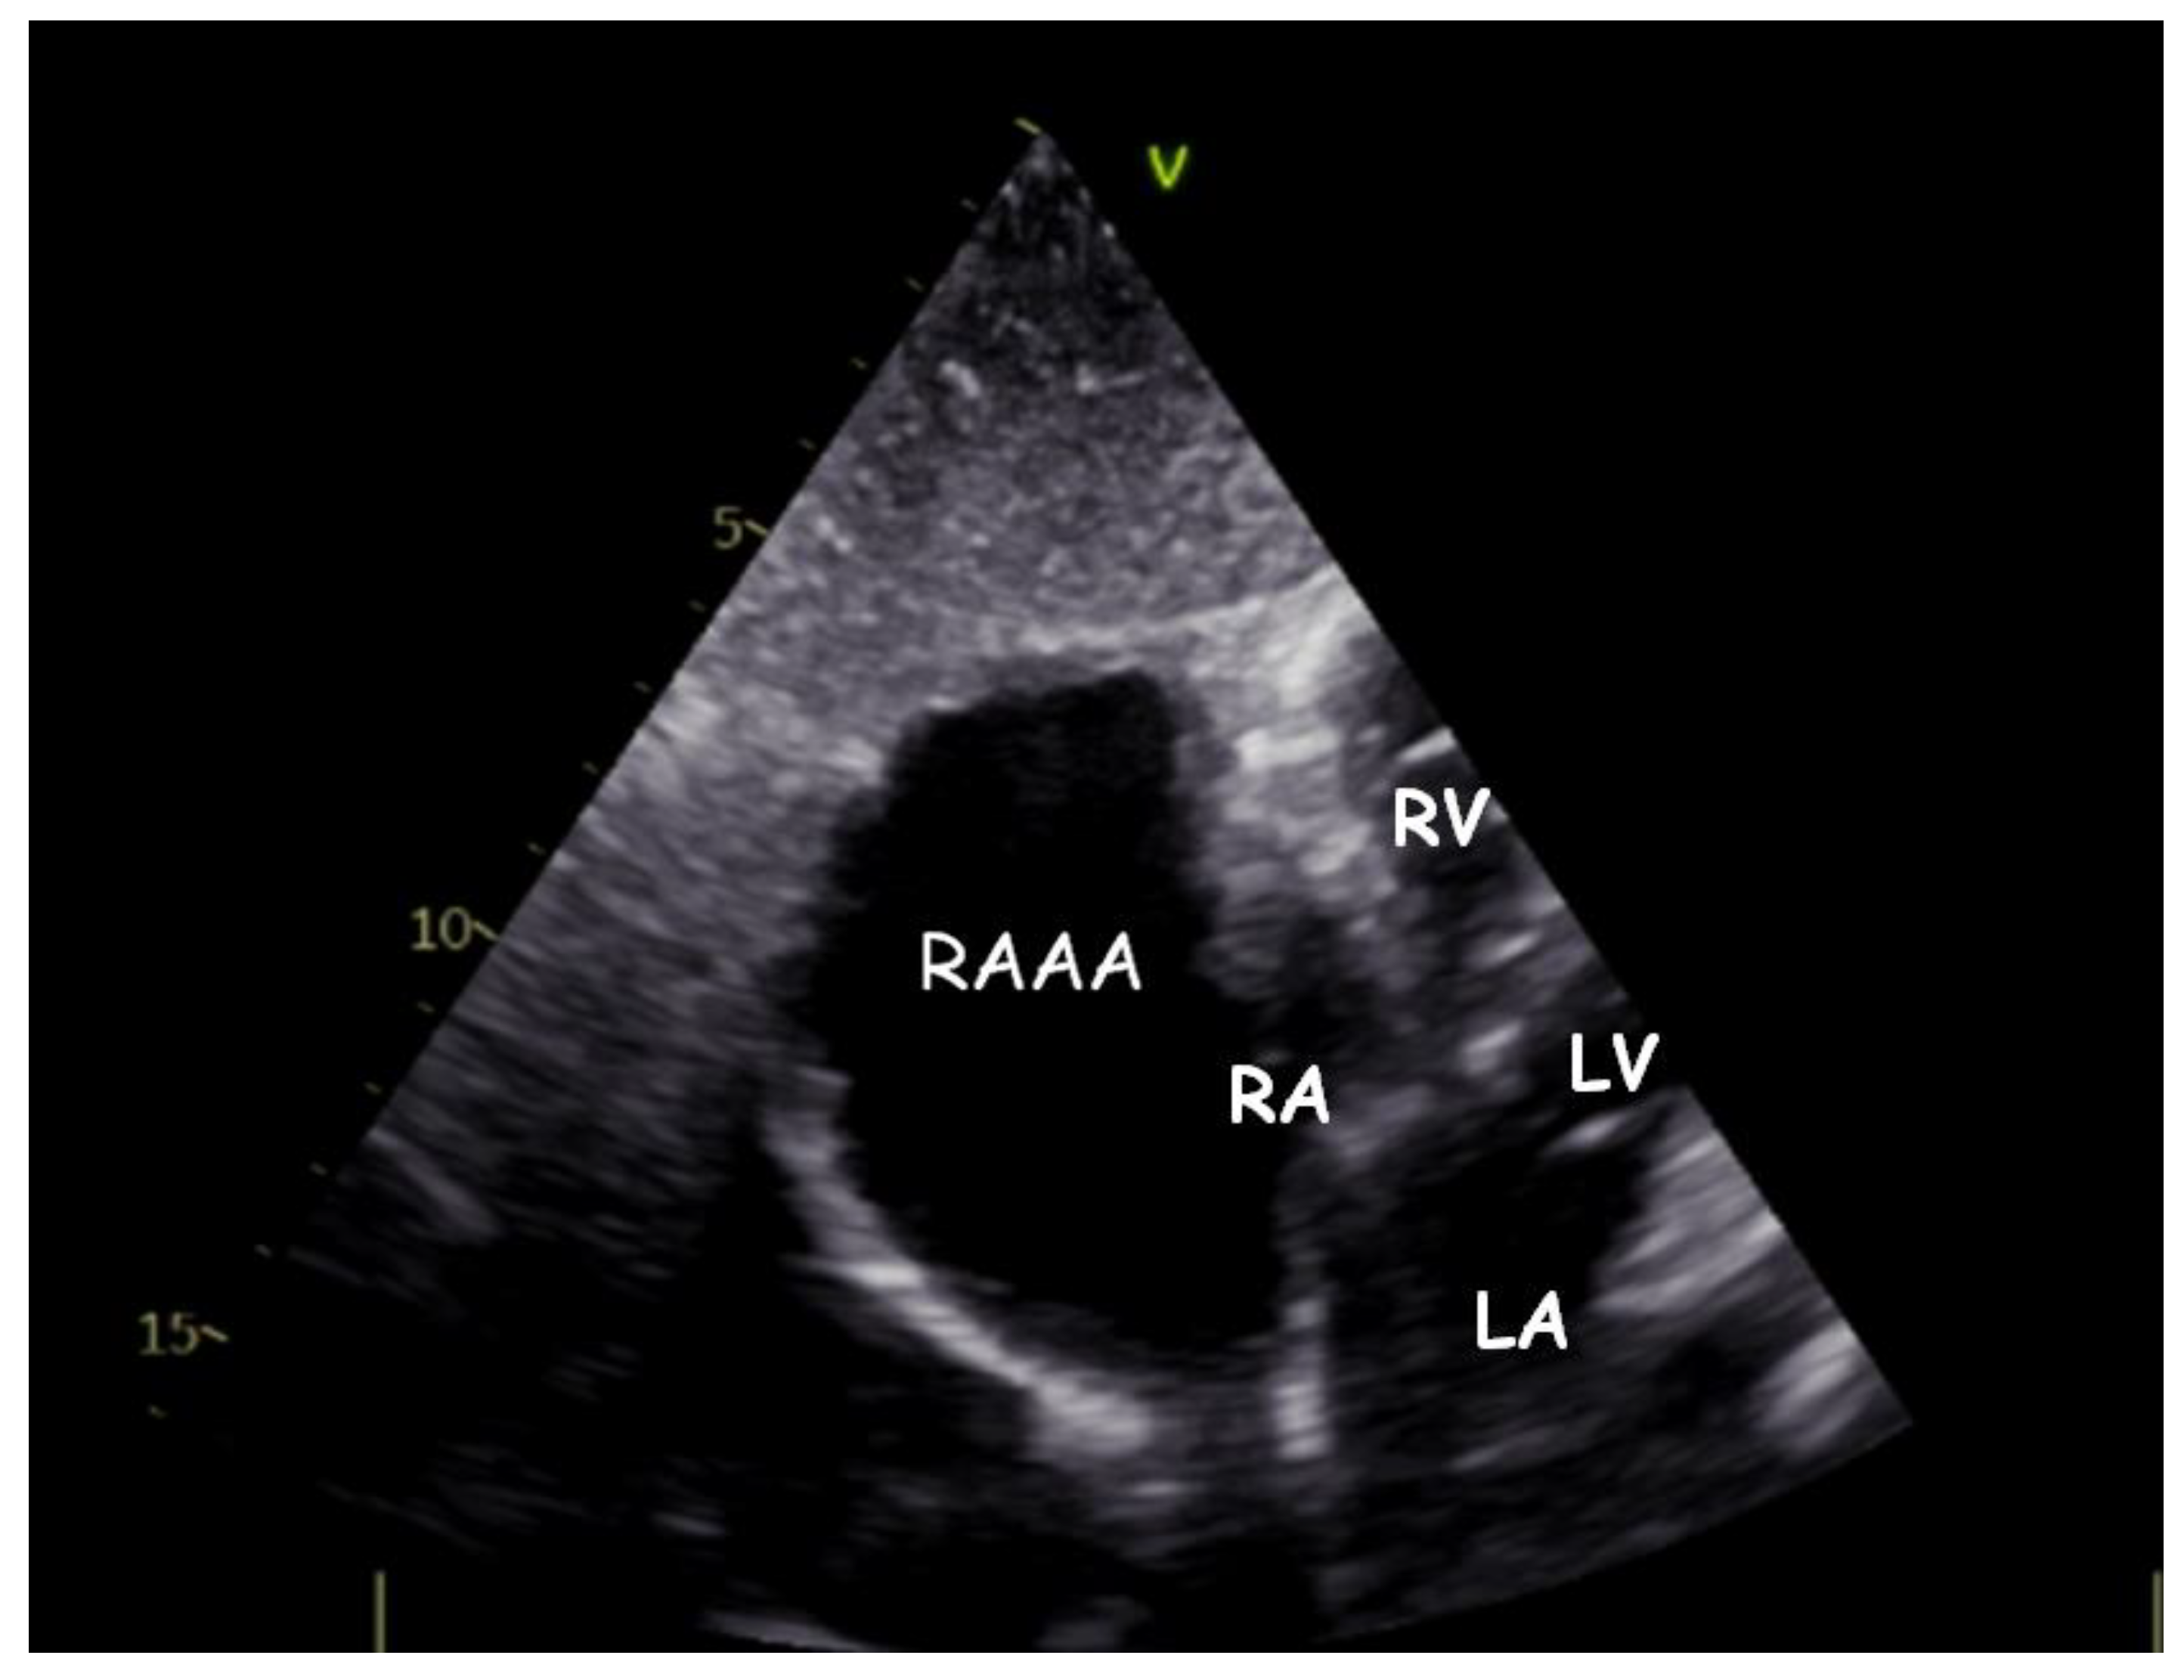

A Gigantic Congenital Right Atrial Appendage Aneurysm in an Infant: Ten-Year Follow-Up

1. Clinical Presentation